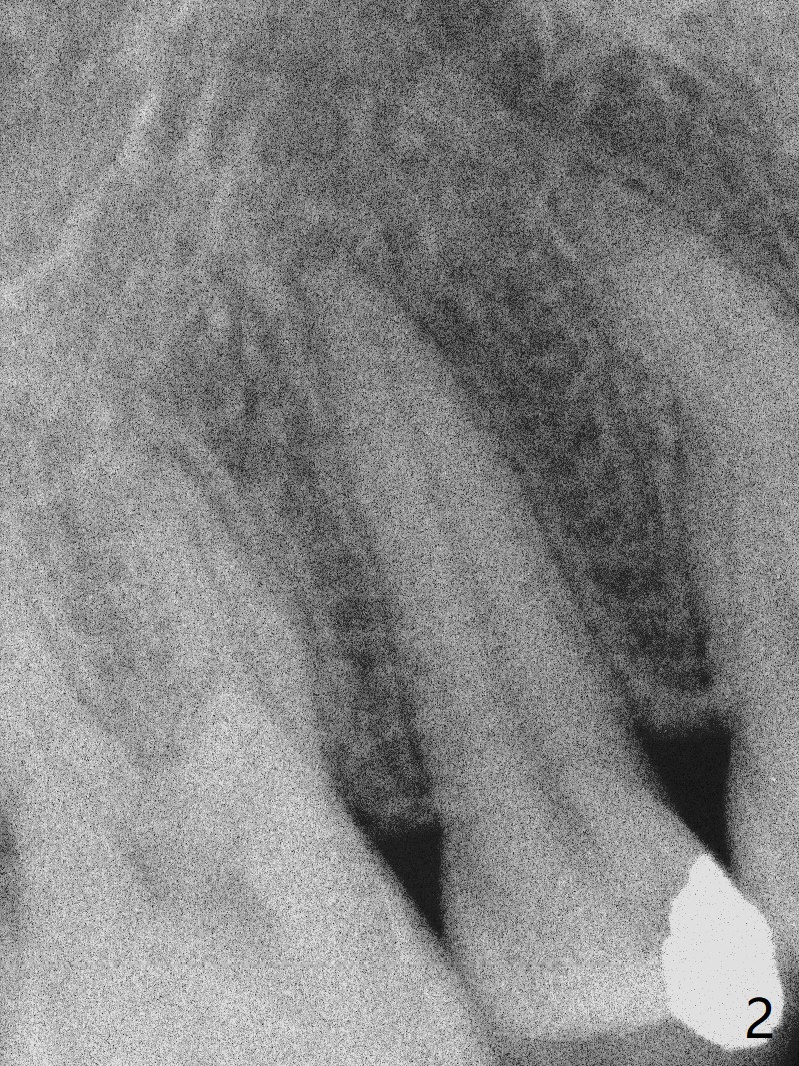

A 29-year-old woman presented to office with multiple amalgam restoration 7 years ago. The tooth #4 developed acute pulpitis 7 months later (Fig.2). The tooth has 2 fused canals; after RCT, composite was placed; after discussion, the patient chose no crown (Fig.3). There is no recurrent periapical radiolucency or tooth fracture 2.5 (Fig.4) or 6.5 (Fig.5,6) years postop.